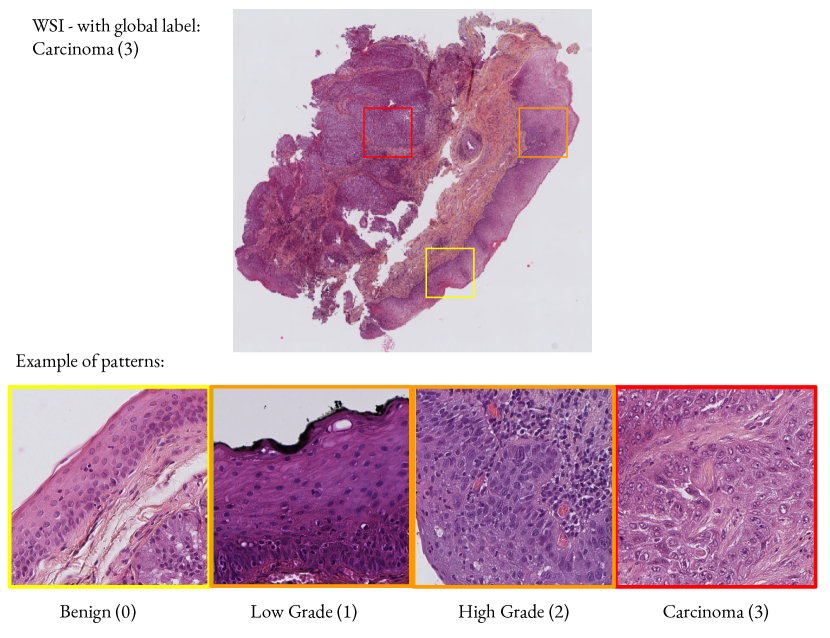

Grading WSI is a difficult task: often, the borders between each grade are blurry and related histologic patterns overlap. Additionally, several grades of lesions can co-exist on the same WSI. In this study we focused on grading head and neck precancerous and cancerous lesions with respect to their gravity. Such lesions are graded by assessing several morphological and cytological abnormalities of the tissue according to the WHO recommendations El-Naggar et al. (2017). Head and neck epithelium can be either normal/benign (0), or present a low grade lesion (1), a high grade lesion (2) or have infiltrative carcinoma (3). (See Appendix A.1 for examples).

A.1 Grading of head and neck precancerous lesions

fig:lesions